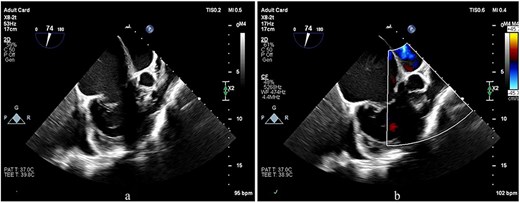

Preoperative transesophageal echocardiography (TEE) demonstrated marked RV and RA enlargement, severe RV systolic dysfunction, thickened RV walls, severe TR due to annular dilation, and severe PV stenosis. No ventricular septal defect was observed preoperatively (Figs 1–3). The left ventricle (LV) appeared small and D-shaped, consistent with elevated RV pressures (Table 1).

TEE images focusing on the RVOT and PV. (a, b) The images show doming of the PV, a prominent muscular bundle beneath the PV, and supravalvular narrowing, resulting in flow acceleration across all these levels.